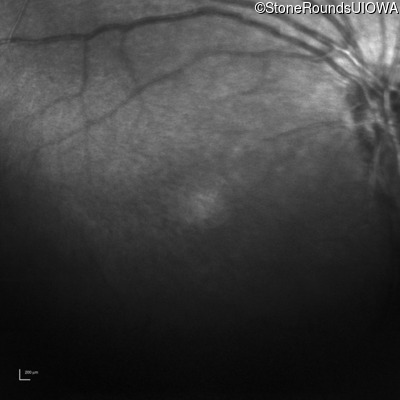

Infrared Fundus Photograph - Left - 10/40

Exemplar